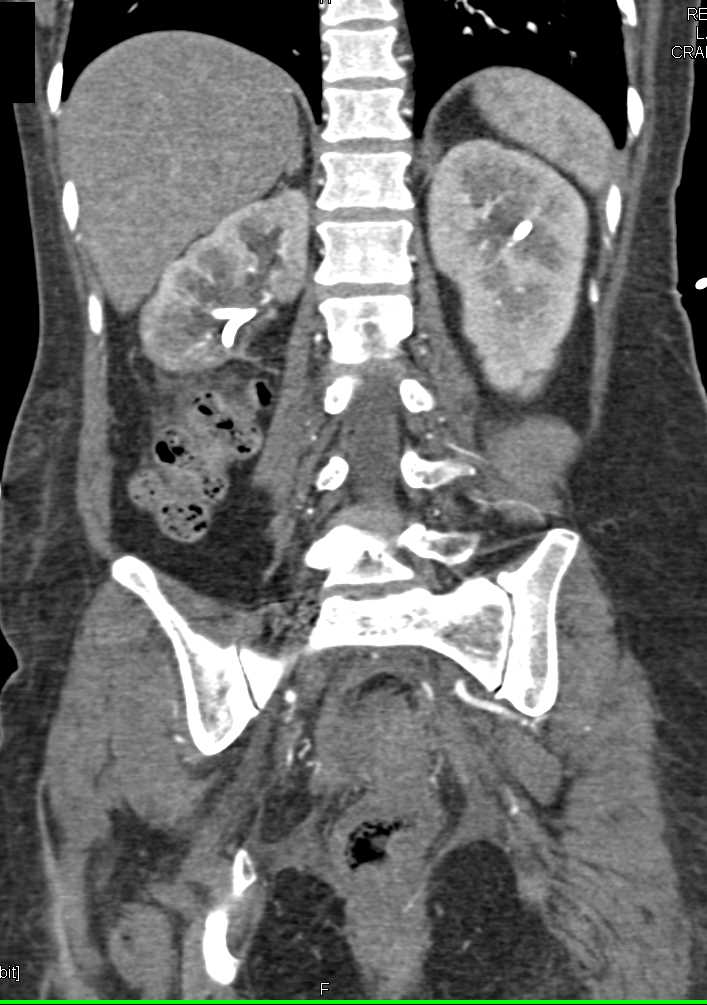

Acute Pyelonephritis Right Kidney